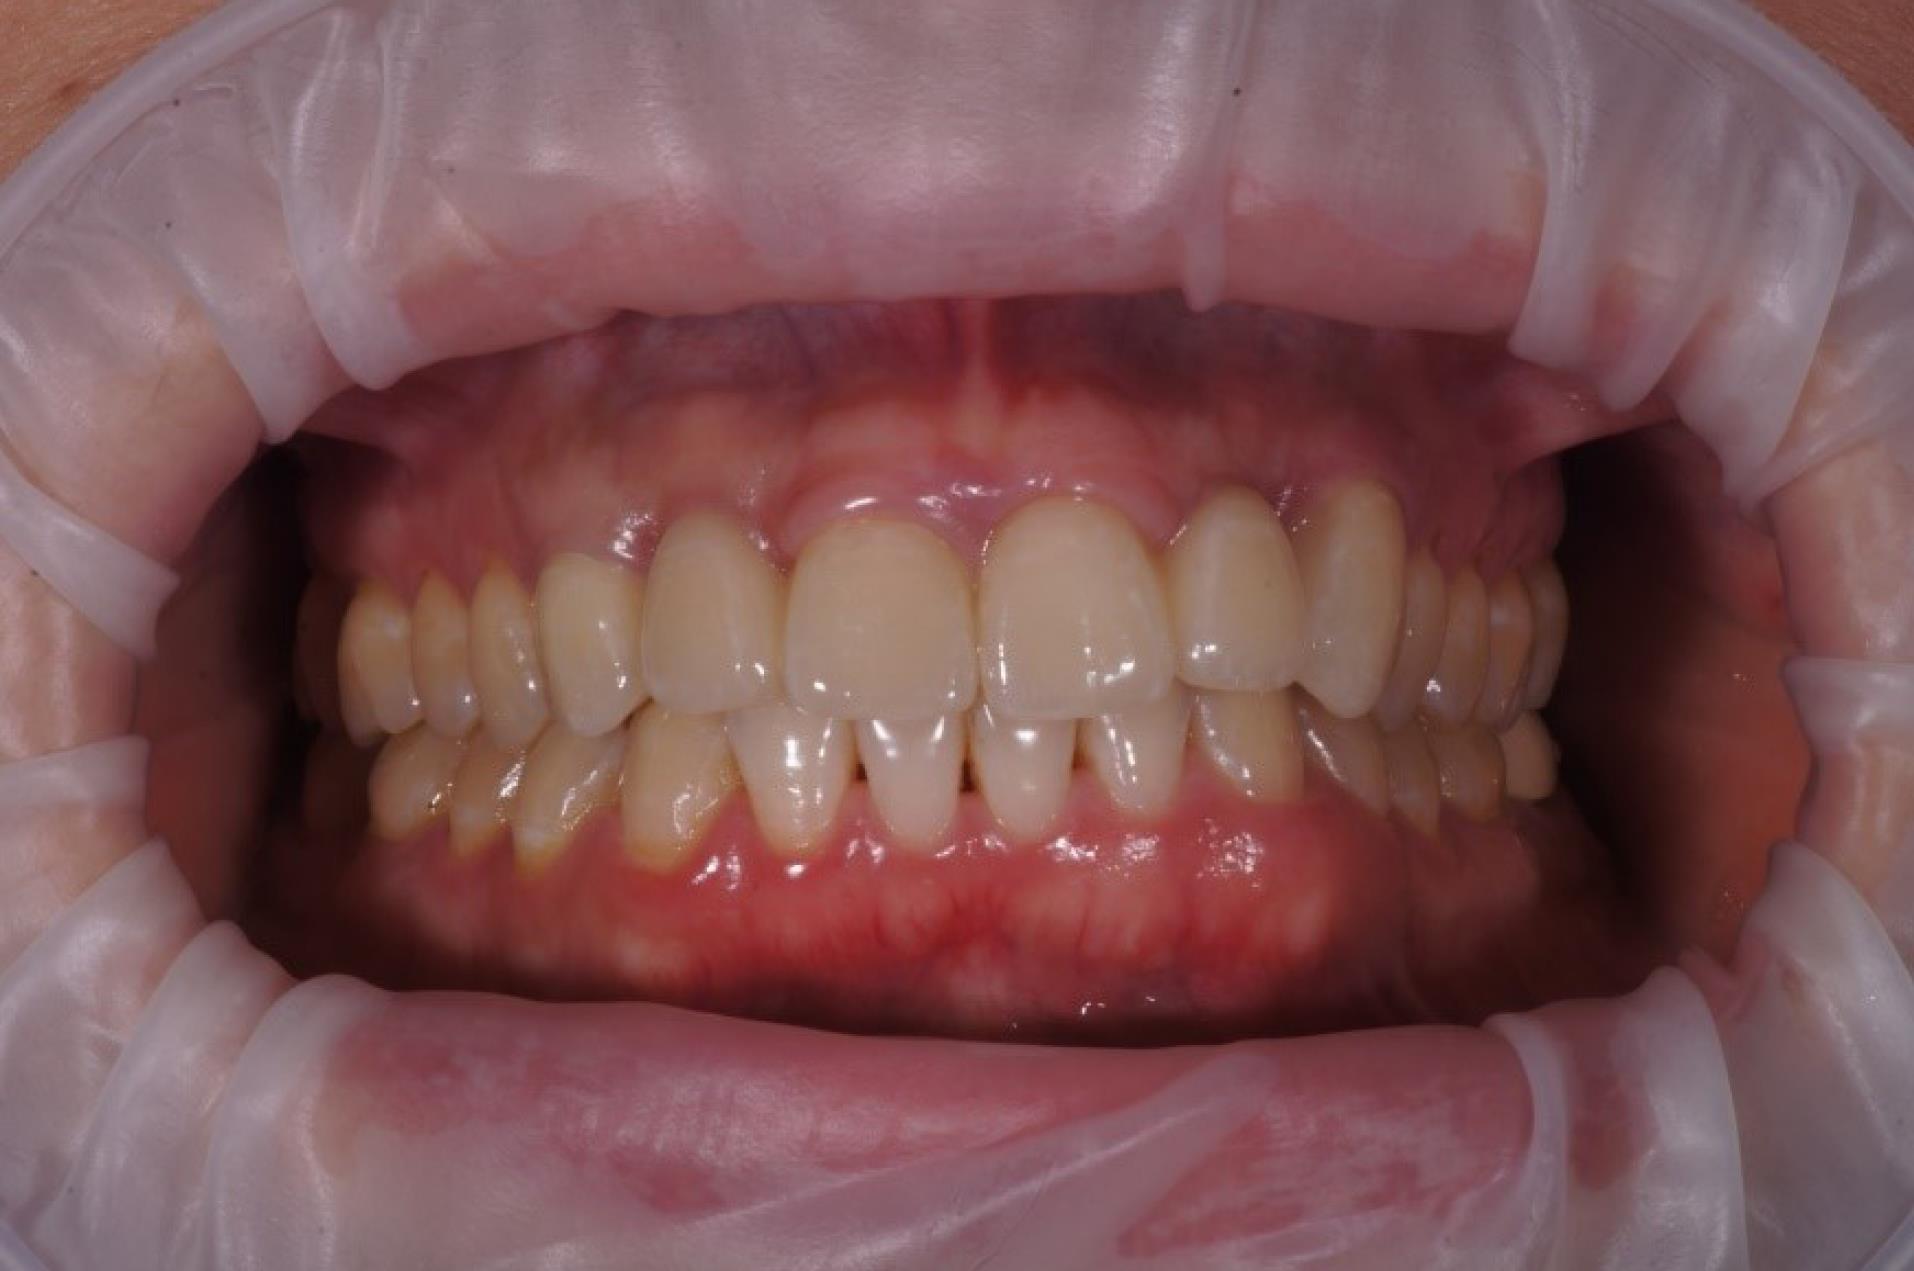

Final restoration

After 4‒6 months, the osseointegration and maturation of the gingival flap were completely developed. The soft tissue contour around the dental implant was corrected by fabricating the old provisional crown or making a new crown, considering the desired result. A digital protocol was routinely used to fabricate provisional transocclusal crowns based on dental implants. The provisional crown was used to facilitate processing and control the pressure force. The criterion for proper pressure on the mucosa during profiling was the presence of mild ischemia, which resolved after 10‒15 minutes. If ischemia persisted, the volume of the provisional crown was corrected to achieve the desired effect. After the final shape of the gingival profile was formed around the implant, a final prosthesis was fabricated. Both digital and analog techniques were used to fabricate final crowns. The impression copings or scan markers were individualized by copying the soft tissue contour onto them immediately after removing the provisional crown with a liquid composite. In the classic variant of fabricating provisional structures, a combination of an individualized zirconia abutment and a ceramic crown was used. The type of ceramic crown was selected depending on each patient’s occlusal and esthetic characteristics (Figures 7, 8, 9, and 10).

Figure 7.

Orthopedic step

Figure 8.

Temporary crowns